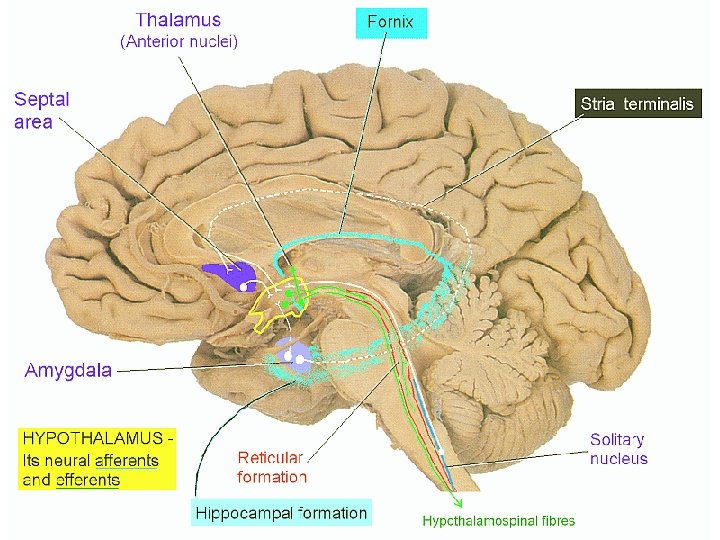

Hypothalamus – bílá hmota • fornix → corpus mammillare (nuclei corporis mammillaris) → tractus mammillaris princeps /rozdvojí se na/ → tractus mamillothalamicus → ncl. anteriores thalami → tractus mammillotegmentalis RF mozkového kmene (ncl. Guddeni) • stria terminalis corpus amygdaloideum → hypothalamus • stria medullaris thalami hypothalamus habenula

Hypothalamus – bílá hmota • fasciculus medialis telencephali = fasciculus prosencephalicus medialis = medial forebrain bundle (MFB) – mezi mediální a laterální zónou jader – propojují hypotalamus s korovým limbickým systémem + limbickým systémem mozkového kmene (+ RF) • pedunculus mammillaris - spojuje corpora mammillaria a nucleus dorsalis tegmenti Guddeni (v RF mesencephala) a fasciculus longitudinalis posterior Schützi ncl. v mediální zóně hypotalamu → autonomní jádra hlavových nervů (příp. až do míchy)